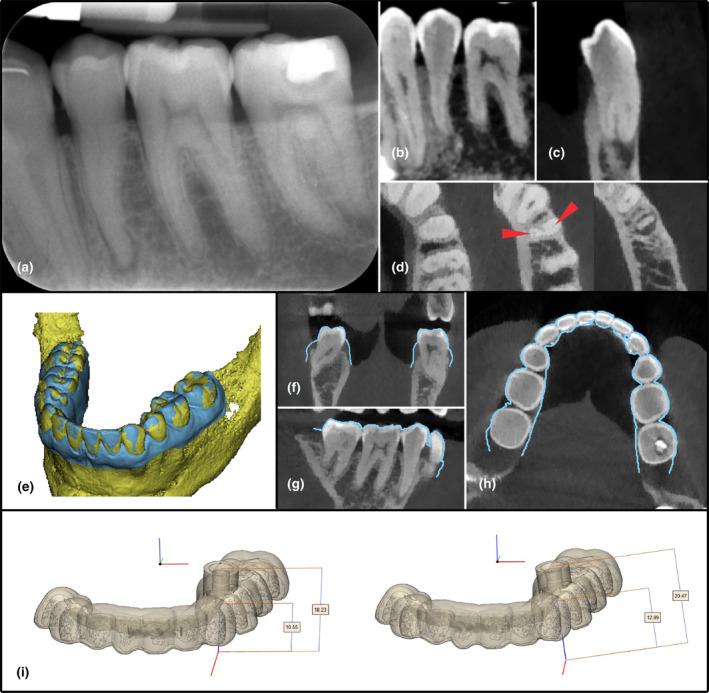

This trial was registered in the ISRCTN.com registry (ISRCTN75277265) and designed as a controlled clinical trial: Single arm trial, prospective, nonrandomized, single-centre study (ethical approval number S64630). Inclusion criteria were; tooth presenting with PCO and symptoms and/or signs of apical periodontitis (AP). An external control group was selected from clinical records of patients presenting the same criteria but treated freehanded. Guided root canal treatments were performed by the same operator on all patients. Freehanded treatments were performed by a specialist in endodontics under microscope with pre-operative CBCT available. Primary outcome for both groups was evaluated as: canal found, canal not found, or perforation. As secondary outcome, the qualitative accuracy of the drill path was assessed as: optimal precision, acceptable precision or technical failure. Patients were followed up yearly. Descriptive statistics on the study patient's demographics and healing outcome were performed and specific statistical analysis was performed on each outcome variable.

A total of 133 teeth were included (n = 60 guided, n = 73 freehanded) from 128 patients (n = 59 guided, n = 69 freehanded). The primary outcome for the guided group was: 59 teeth canals found and 1 tooth canal not found. No perforations were recorded. In the freehanded group, the root canal was successfully found in 59 teeth, seven were not found, and seven had a perforation. An analysis of all data showed that guided endodontics presented statistically significant better outcome than freehand treatment (p < .05).